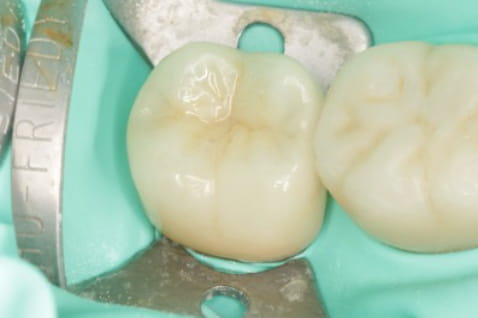

根管の中を封鎖し、根管治療終了

根管治療が終わったところが、また隙間から感染しないように、

上から被せを精密に接着させ、密封。

治療後病気がなくなり骨が再生した